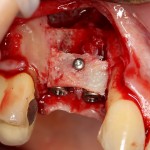

После установки второго импланта в правильное положение (ориентируемся по оси и форме лунки зуба), внешнюю кортикальную стенку восстанавливаем костным фрагментом, получившимся после синуслифтинга:

На деле — ничего сложного. Костный фрагмент просто фиксируется одним винтом. Таким образом восстанавливается отсутствующая костная стенка.

Субантральное пространство и пустые полости между костным блоком, имплантами и принимающим ложем заполняется аутокостной стружкой и закрывается мембраной BioGide: